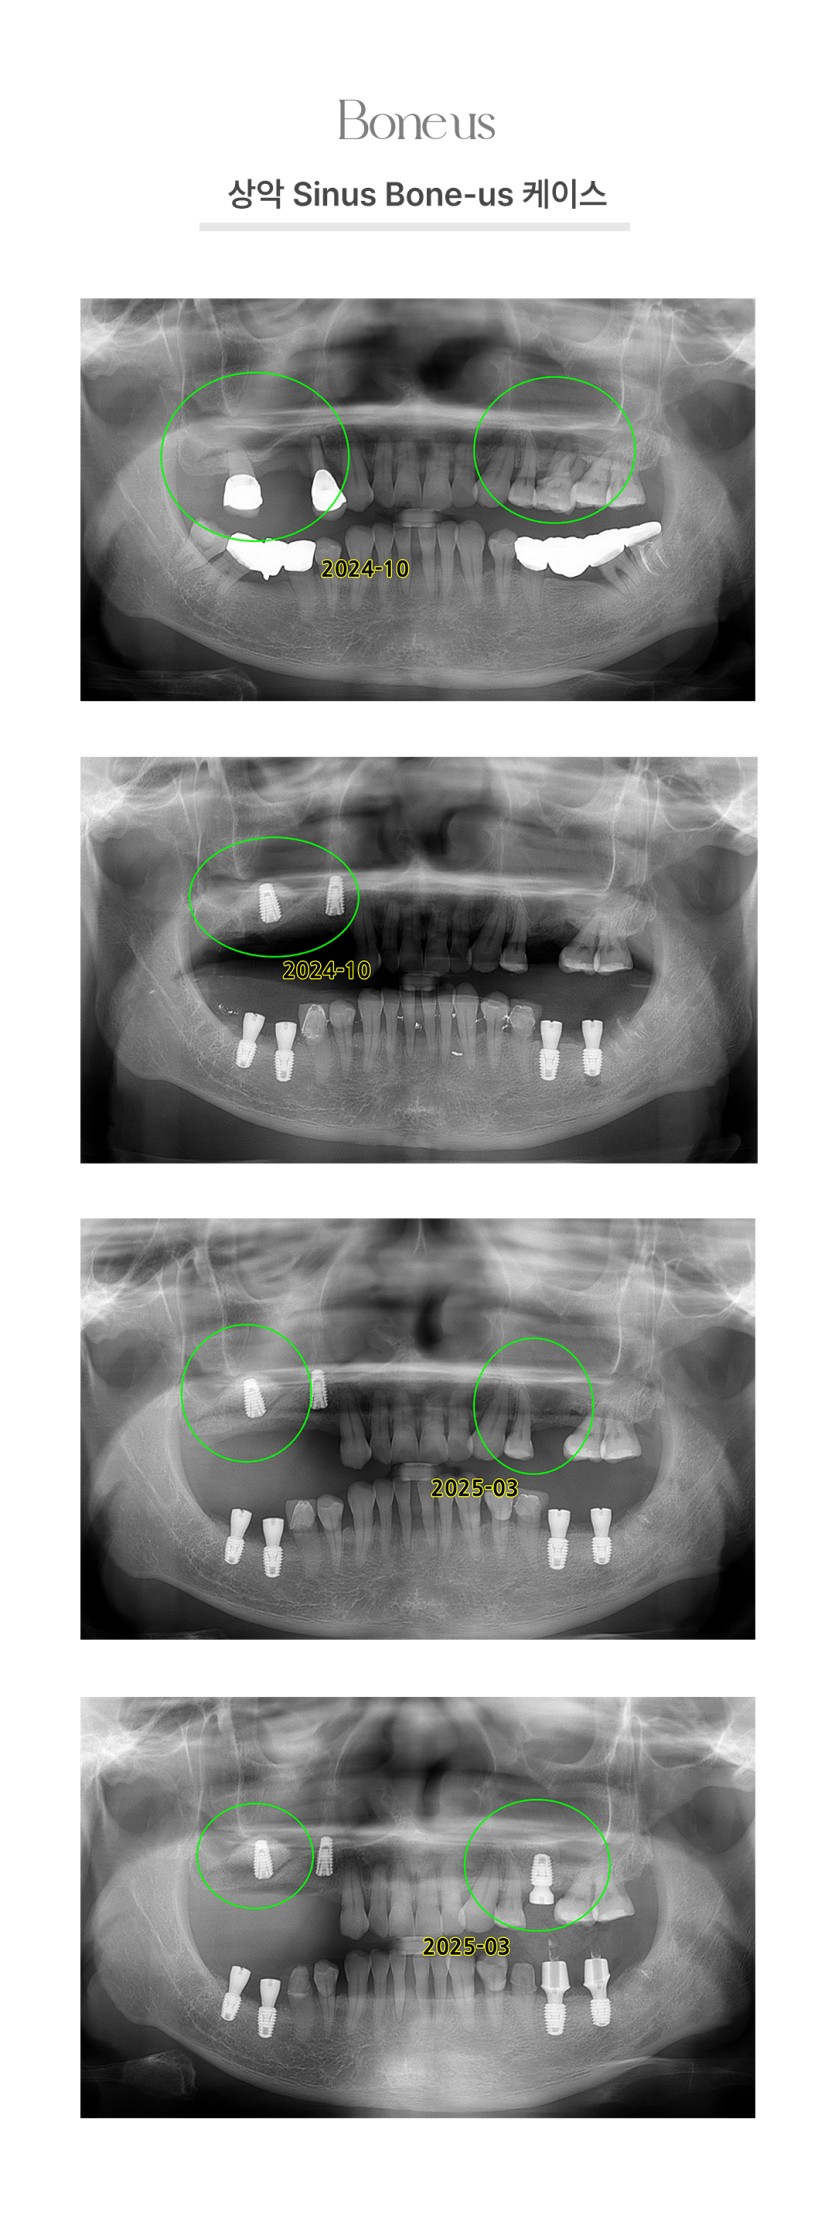

CLINICAL CASE

본어스 시술사례

상악 Sinus 본어스 케이스 2

상악 Sinus 본어스 케이스